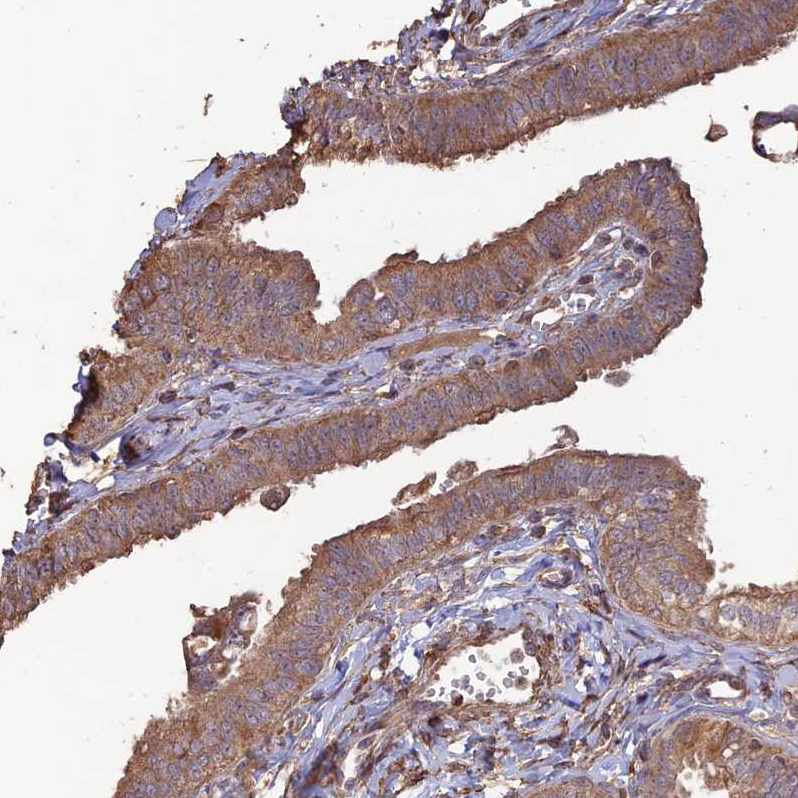

Immunohistochemical staining of human prostate shows moderate to strong cytoplasmic positivity in smooth muscle cells.